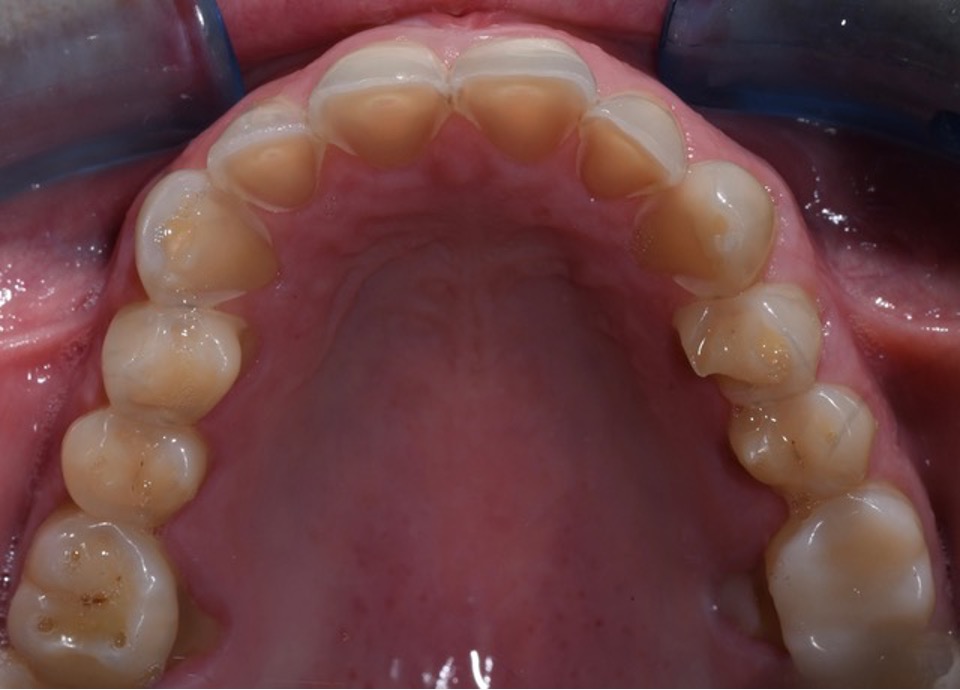

Per una visualizzazione immediata delle caratteristiche morfologiche dell’erosione dentale, ecco due esempi clinici che illustrano le differenti fasi del processo erosivo e le relative implicazioni diagnostiche.

Caso B

Erosione BEWE rischio basso (3-8)

Bulimia nervosa per 3 anni, ad oggi risolta.